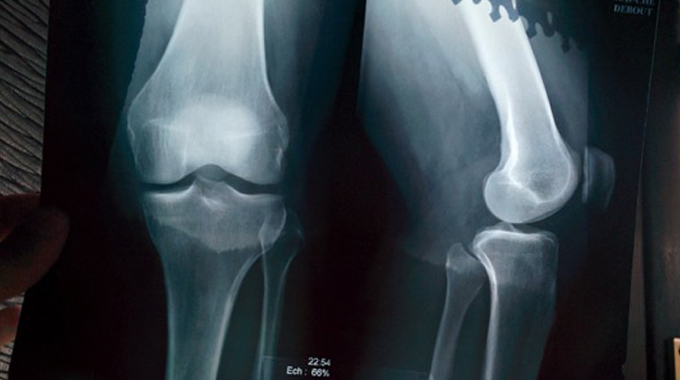

Avid mountain biker and adventurer, Sarah Wylie, found out the hard way after suffering a knee injury and having to lay off the bike and lay up her pedalling pins. She shares her story with TWC, and how life beyond the bike has been…